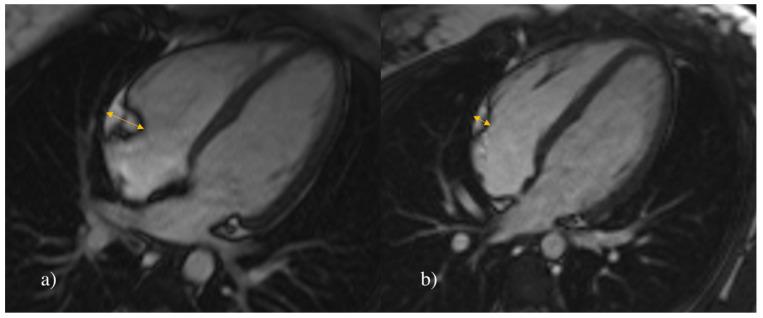

Epicardial adipose tissue (EAT) is a metabolically active tissue located on the surface of the myocardium, which might have a potential impact on cardiac function and morphology. The aim of this study was to evaluate whether EAT is associated with essential arterial hypertension (AH) in children and adolescents.

Prospective cardiovascular magnetic resonance (CMR) study and clinical evaluation were performed on 72 children, 36 of whom were diagnosed with essential AH, and the other 36 were healthy controls. The two groups were compared in volume and thickness of EAT, end-diastolic volume, end-systolic volume, stroke volume, left ventricular (LV) ejection fraction, average heart mass, average LV myocardial thickness, peak filling rate, peak filling time and clinical parameters.

Hypertensive patients have a higher volume (16.5 ± 1.9 cm and 10.9 ± 1.5 cm ( = -13.815, < 0.001)) and thickness (0.8 ± 0.3 cm and 0.4 ± 0.1 cm, (U = 65.5, < 0.001)) of EAT compared to their healthy peers. The volume of EAT might be a potential predictor of AH in children.

Our study indicates that the volume of EAT is closely associated with hypertension in children and adolescents.